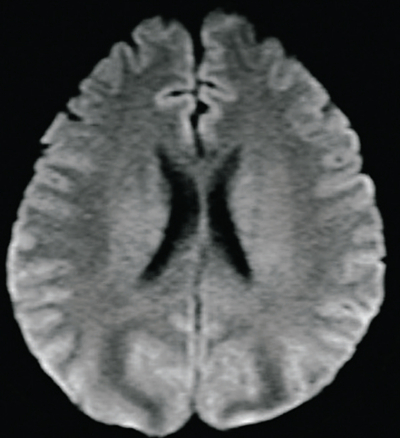

搬入時の意識レベルは JCS Ⅰ-2。けいれんは治まっていた。体温 37.2 ℃。心拍数 82/分。血圧 164/96 mmHg。呼吸数 20/分。 SpO₂ 96%(マスク 5L/分酸素投与下) 。頭部MRIの T2強調像及び拡散強調像とを別に示す。

この患者の脳にみられる病態はどれか。

e. 浮腫